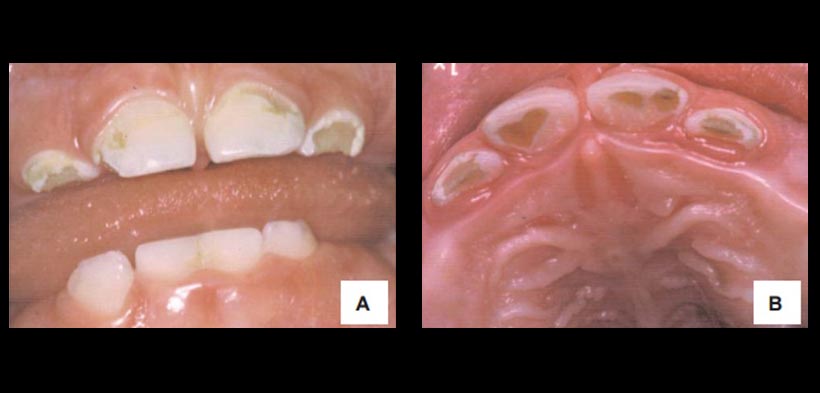

Fig. 1. Caries de infancia temprana: A) Estadio moderado: alteración temprana de las superficies lisas vestibulares de los dientes antero- superiores, manteniéndose sanos los inferiores. B) aspecto de la superficie palatina.